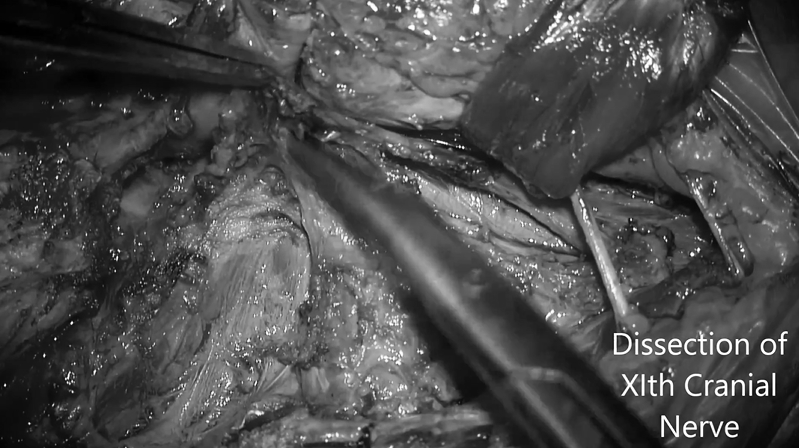

▼识别并解剖十一颅神经

▼暴露C1寰椎横突